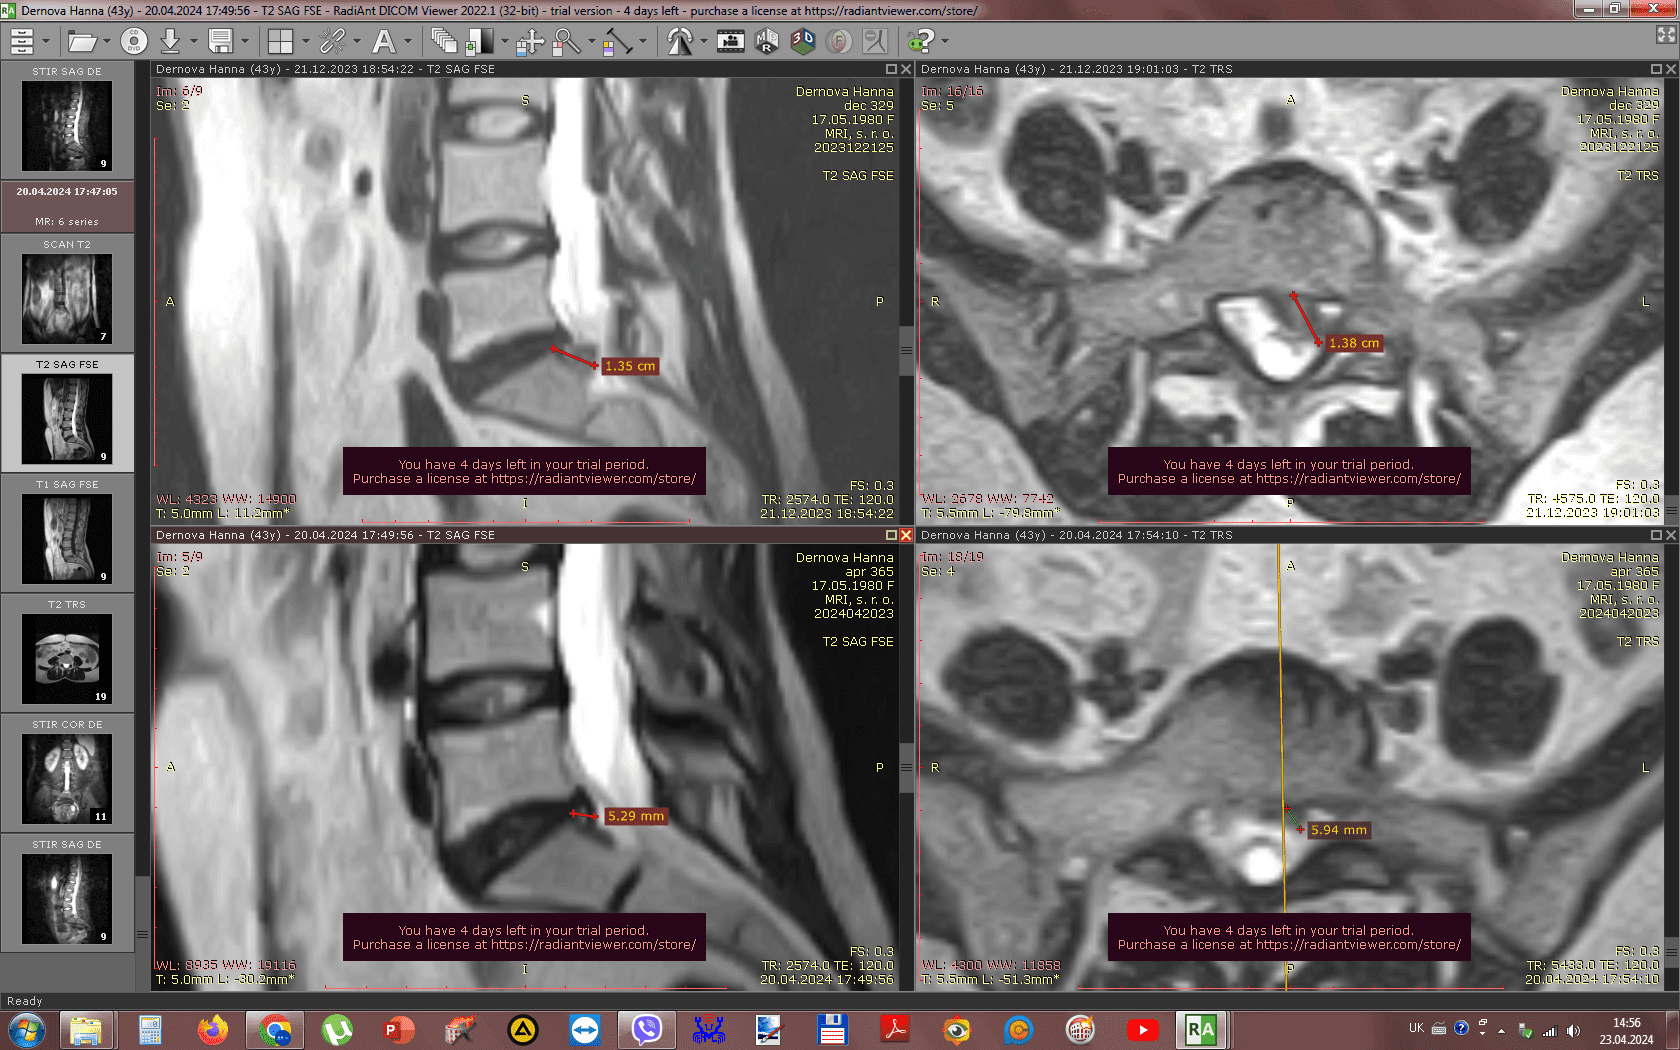

Метод лікування грижі шляхом стимуляції резорбції в Україні був впроваджений у 2020-2021 роках.  Алгоритм оцінки грижі на предмет резорбції, що використовується у клініках – є авторським, розроблений лікарем Боханом А.Ю.